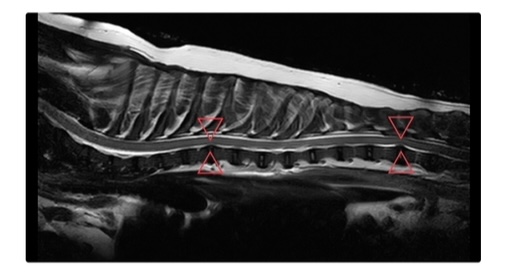

椎間板ヘルニアのMRI

上の画像は胸部および腰部の椎間板ヘルニアを発症した犬(トイプードル、6歳齢、避妊雌)のMRIです。▽△で示した部分の椎間板が脊髄を圧迫しています。

このワンちゃんは、元気がなく、どこか痛そうにしているとの事で来院しました。エックス検査、および神経学的検査等により椎間板ヘルニアが疑われたため内服薬による治療を開始し、後日MRI検査を行いました。

MRI検査では正確な病変部位を確認することができます。検査後、PLDDによる減圧術を実施しました。PLDDとは、病変部へのレーザー照射によって髄核を蒸散させることで椎間板内圧を下げ、脊髄への圧迫を軽減する低侵襲治療です。